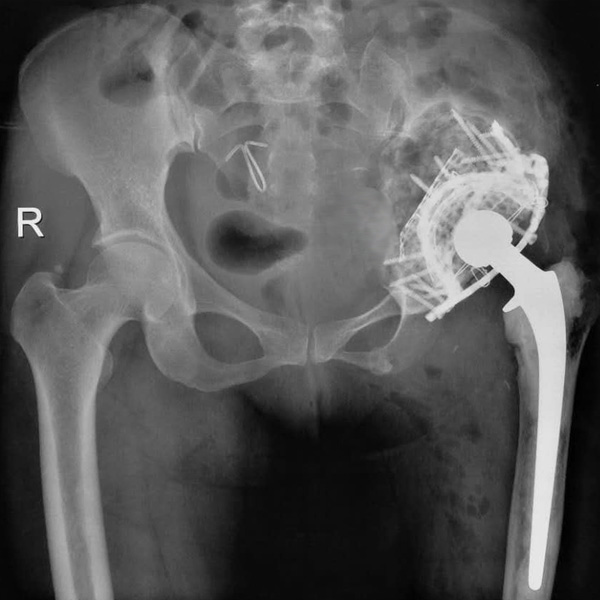

髖關(guān)節(jié)翻修

患者蘇某,女性,11年前因“左髖關(guān)節(jié)屈曲攣縮畸形”行左側(cè)人工全髖關(guān)節(jié)置換,近來(lái)感覺(jué)左髖關(guān)節(jié)疼痛,不敢行走,經(jīng)“攜生醫(yī)療平臺(tái)”就診于哈......